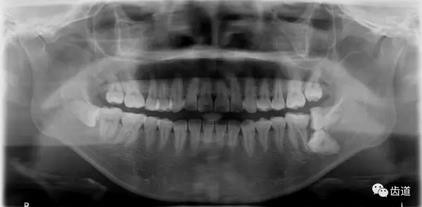

下頜第二第三磨牙阻生口腔曲面斷層片影像

下頜第二第三磨牙阻生CBCT影像定位

三種圖片的影像學(xué)比較